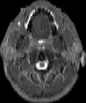

Visible Human male: Sectio transversalis 1171

CT